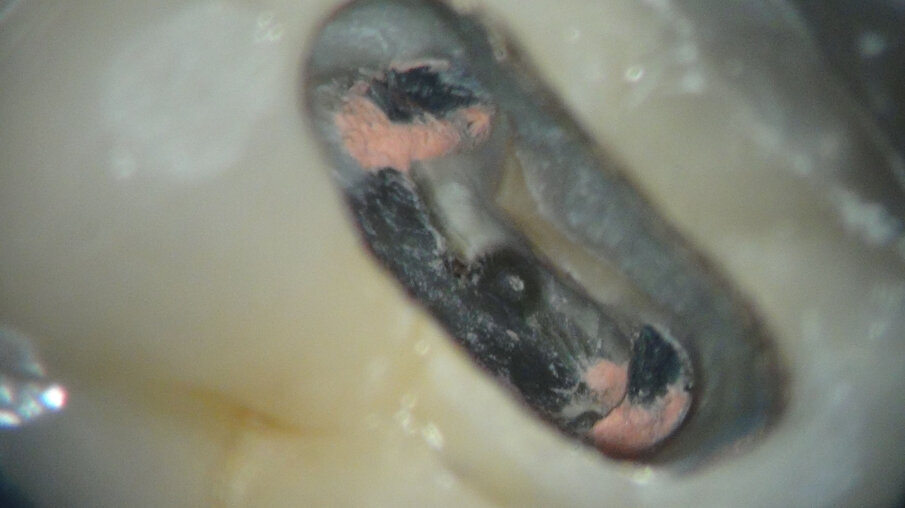

Na anesthesie en rubberdam maken we de access (afbeelding 8 en 9). De zwarte plastic Thermafil carriers zijn duidelijk te zien. Na wat gutta verwijderd te hebben, blijft er op de isthmus iets guttapercha achter. Zou ik dan toch vier jaar geleden een MidMesial gemist hebben (afbeelding 10)? We richten onze inspanningen eerst op de midmesial. Een uur later geef ik het op. Ik durf ook niet verder af te dalen in het relatief smalste deel van de mesiale radix. Het gevaar op een perforatie wordt me te groot (afbeelding 11 en 12).

Afbeelding 8. Na anesthesie en rubberdam maken we de access.

Afbeelding 10. Het is mogelijk dat we 4 jaar geleden een MidMesial gemist hebben.